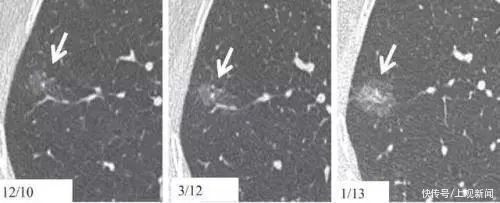

肺结节在CT片上表现为小的、局限性、类圆形、密度高的阴影,可单个或多个。边界清楚、影像不透明、直径小于或等于3cm的结节,无肺门增大或胸腔积液的表现。

Lung nodules appear on CT scans as small, localised, quasi-circular, dense shadows of single or multiple counts. These nodules are singular, well-defined, opaque in images, with diameters of 3cm or less, and show no signs of hilar enlargement or pleural effusion.

毛玻璃样结节是一种影像学表现,是指局部结节样区域,肺的模糊度增加,表现为密度轻度增高的云雾状淡薄影或圆形结节,样子像磨砂玻璃一样,所以叫毛玻璃样结节。

GGNs are imaging manifestations that refer to a localised nodule-like area with increased lung ambiguity, showing as a nebulous faint shadow or round nodule with mildly increased density. They have the appearance of ground glass, hence the name ‘ground-glass nodules’.

单纯磨玻璃样变恶性率高达59%-73%;混合性磨玻璃样病灶恶性率>93%

因为毛玻璃结节有可能是早期肺癌,我们不能放任其发展,及早的采取措施,防止向周围及远处脏器转移,甚至造成更为严重的后果。

The malignancy rate of pure GGNs is as high as59%-73%; the malignancy rate of mixed GGN lesions isgreater than93%.

Since GGNs can be early-stage lung cancers, we must intervene by taking early measures to prevent it from metastasizing to surrounding and distant organs, or leading to even more severe consequences.

孤立的纯毛玻璃样肺结节:如果小于5mm,一年随访一次;如大于/等于5mm,3个月后复查CT,至少每年1次肺CT检查,观察结节大小性质变化。肺部毛玻璃结节一般主张大于8mm,结节形态欠规则,边缘存在分叶,毛刺等恶性征象就需要手术切除。

Solitary pure GGNs: if it is smaller than 5mm, follow up once a year; if it is 5mm or larger, CT scan re-examination after 3 months, and lung CT scan at least once a year to observe changes in size and nature. Excision is required if malignant symptoms appear, such as:GGNs in the lungs become larger than 8 mm, irregular nodule shapes, lobulated margins, and jagged edges.